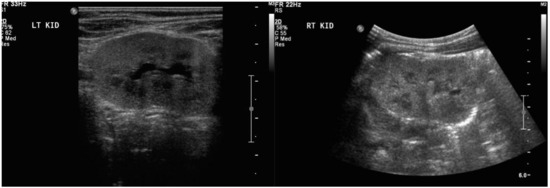

In order to study the potential for suPAR to transfer from the mother to the fetus, we performed an in vivo study wherein 100 μL saline and human histadine (HIS)-tagged suPAR (20 μg) were injected in pregnant mice through their eyes (N = 2 for control saline injection and N = 4 for suPAR injection). Timed breeding was performed and injections were done on embryonic day 16.5. Maternal serum, placenta, and fetal tissue were collected 2 h after injection. Placenta and fetal tissues were lysed in Laemmli buffer for 20 min, then processed with homogenization and sonication (30 s on, 30 s off). suPAR level was determined by ELISA (ViroGates, Birkerød, Denmark). There was prominent transfer of suPAR from the mouse mother to the fetus (Figure 4). The substantially elevated human suPAR in pregnant mice demonstrated the success of injection. A significantly increased suPAR level in placental and fetal tissues indicated that suPAR was able to pass through the placental barrier to reach the fetus.

In our in vivo study, suPAR was injected and tracked in pregnant mice, suggesting that transmission occurred from mother to fetus. Although this finding should be confirmed by a larger study, it is consistent with the lower serum suPAR level noted in our pregnant patient at the time when the fetal content of suPAR was elevated to 4783 pg/mL in the cord blood, as presumably suPAR was being transferred from the mother to the fetus. Concomitantly, both the mother and the fetus displayed elevated integrin activation of podocytes when their sera were incubated with these cells. This finding is consistent with suPAR affecting the glomerular filtration barrier of both the mother and the fetus. Our case supports a permeability factor, such as suPAR, as a potential underlying cause of podocyte injury in primary FSGS and sheds light on the effect of this factor on the fetus. The improvement in the amniotic fluid volume was likely related to the maternal treatment with steroids. The resolution of the newborn’s proteinuria was likely related to complete elimination of the permeability factor by her otherwise normal kidneys.

Figure 4. Maternal serum, placenta, and fetus tissue 2 hours after injection of suPAR.